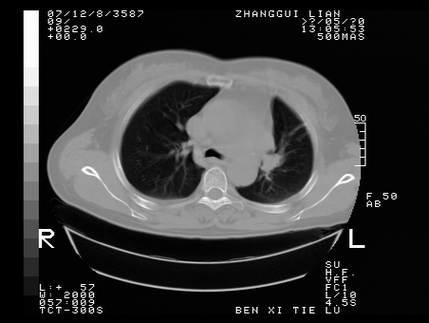

标题: CT10817:女,46,胸疼,无其他病史 [打印本页]

标题: CT10817:女,46,胸疼,无其他病史

左侧上纵隔旁团块影,部分植入纵隔,与纵隔界限不清,另:左肺门明显见团块,气管隆突前方见肿大淋巴结。考虑:左上肺纵隔型肺癌伴左肺门及纵隔淋巴结转移!

首先考虑左侧中央型肺癌伴阻塞性肺炎、纵隔内、弓旁淋巴结转移可能性大(纵隔窗调的欠佳)

1左上肺中心型肺癌伴左肺上叶不张2主动脉弓旁淋巴结转移3左下肺炎症

1 左侧中央型肺癌伴阻塞性肺炎 2 左肺门及纵隔淋巴结转移!3两侧胸腔及心包积液.

左侧胸廓塌陷,纵隔向左侧移位,左上肺不张。